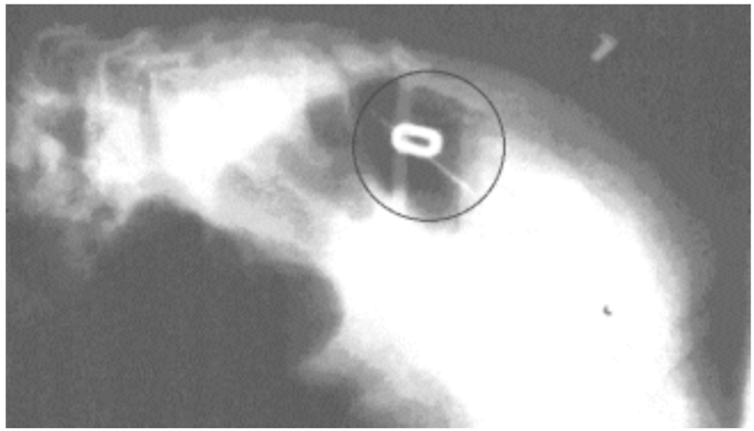

E há situações mais inusitadas, como a de uma jovem paulistana que inalou um pequeno brinco enquanto dormia. Durante anos ela procurou pelo adereço, até encontrá-lo dentro das vias nasais, por acaso, em um raio-X dentário. Apesar de ter precisado de uma cirurgia para a remoção, teve sorte por ele não ter ido parar na laringe, traqueia ou no pulmão. O objeto tinha dimensão suficiente para causar uma obstrução grave e insuficiência respiratória.